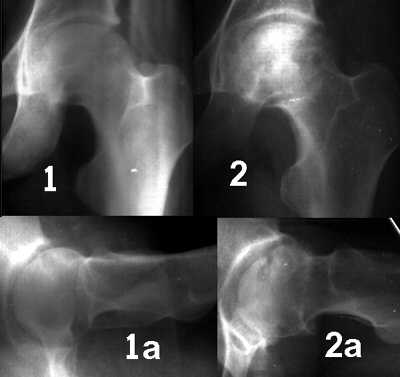

Диагностика ТБС рентгеном и асептический некроз: особенности лечения

Раздел: Снимки-откровения